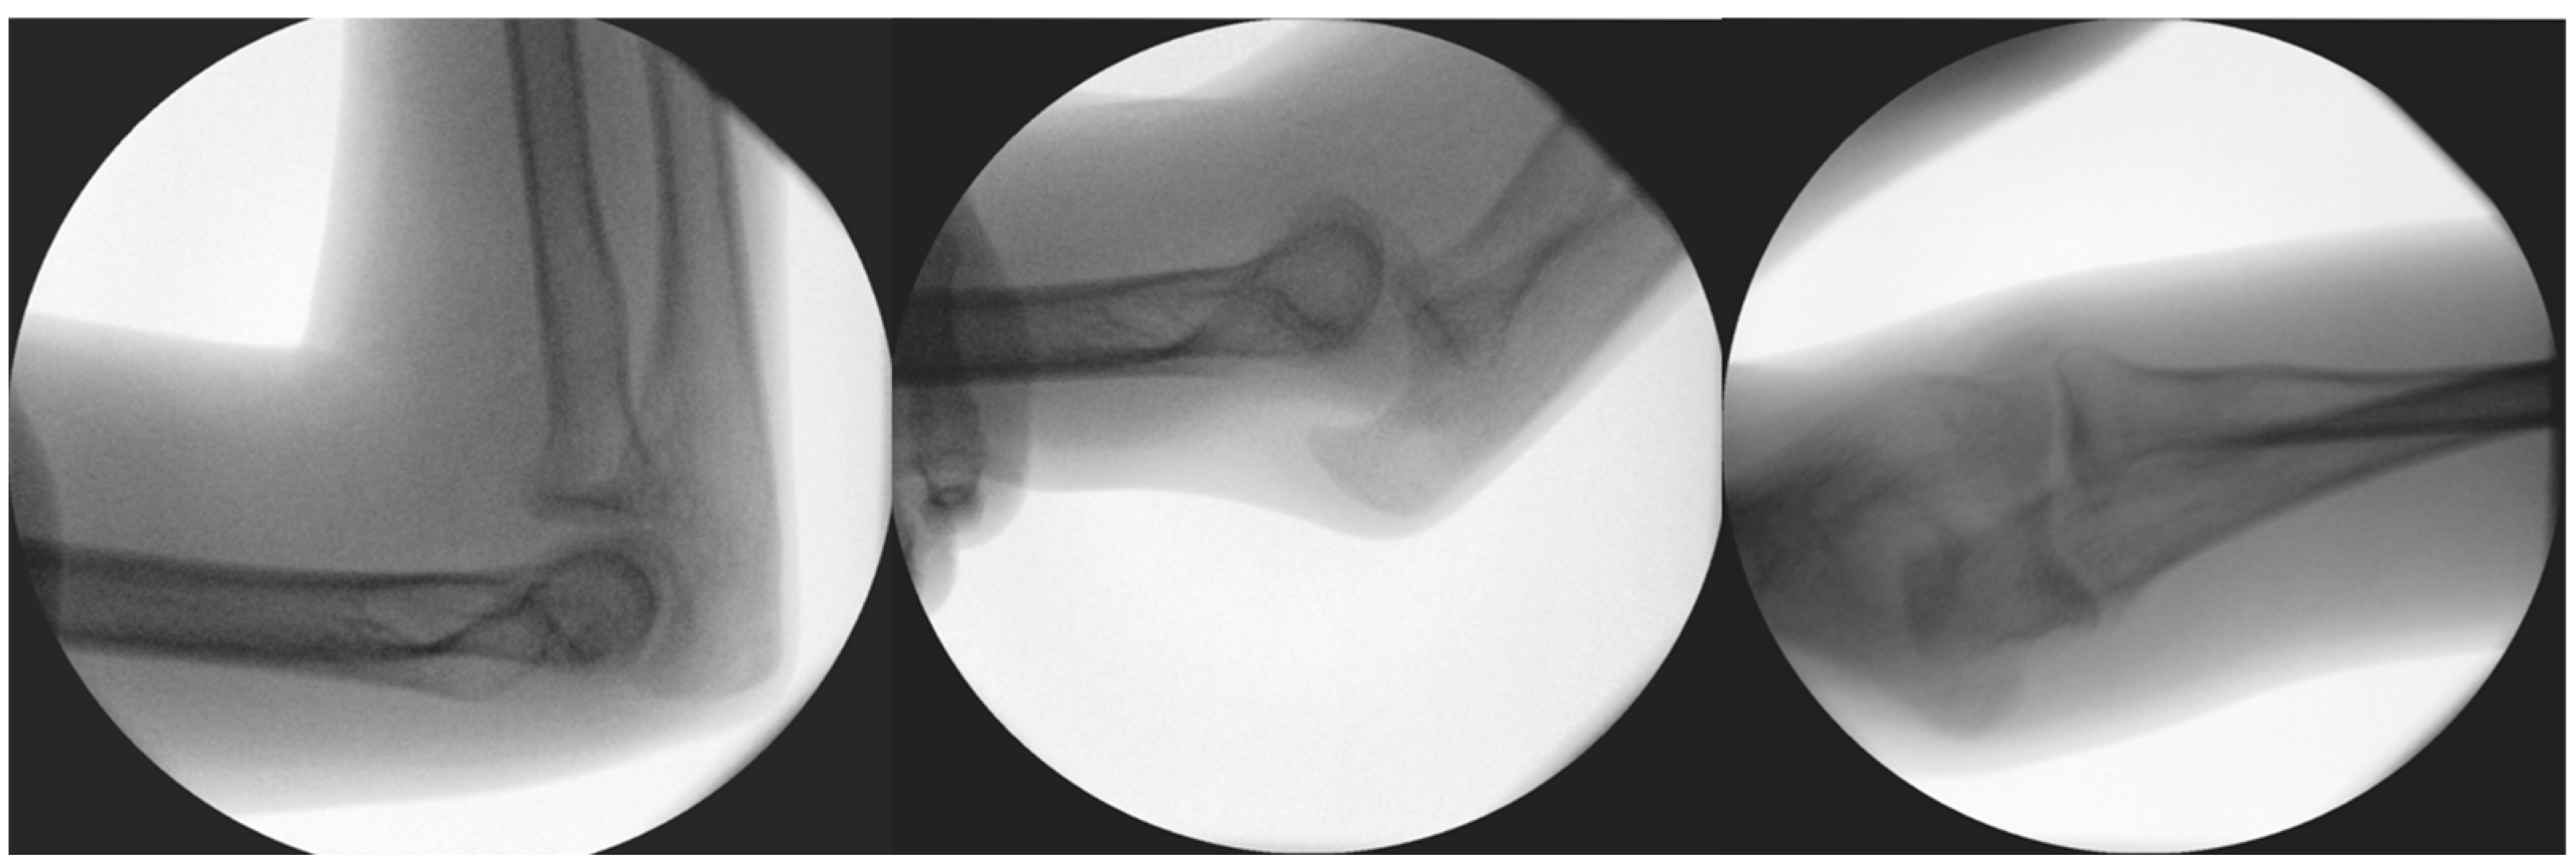

Figure 3.

Results of diagnostic dynamic testing under fluoroscopy.

Diagnostic stability tests were carried out before and after reconstructive surgery, and, until then, an orthosis was provided to prevent the subluxation of the arm. Diagnostic tests were carried out prior to the planned operation under the influence of inhalation anesthesia. These included valgus stress in the 0- (extended), 30-, 60-, and 90-degree (°) positions, to which the medial ligamentous structures responded well by not letting the joint open or be subluxated. In the extended and 90° positions, the dorsally oriented stress test proved stable; however, in the 60° position during flexion, instability was noted, in which the joint was undoubtedly subluxated (Figure 3) while the summary of events can be found in Table 1.